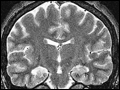

| Figure 369-1 Mesial temporal lobe epilepsy. The EEG suggested a right temporal lobe focus. Coronal high-resolution T2-weighted fast spin echo magnetic resonance image obtained through the body of the hippocampus demonstrates abnormal high-signal intensity in the right hippocampus ( ... | |